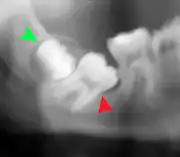

Impacted wisdom teeth are classified by their direction of impaction, their depth compared to the biting surface of adjacent teeth and the amount of the tooth's crown that extends through gum tissue or bone. Impacted wisdom teeth can also be classified by the presence or absence of symptoms and disease. Screening for the presence of wisdom teeth often begins in late adolescence when a partially developed tooth may become impacted. Screening commonly includes a clinical examination as well as x-rays such as panoramic radiographs.

If the tooth cannot be assessed with clinical exam alone, the diagnosis is made using either a panoramic radiograph or cone-beam CT. Where unerupted wisdom teeth still have eruption potential several predictors are used to determine the chance of the teeth becoming impacted. The ratio of space between the tooth crown length and the amount of space available, the angle of the teeth compared to the other teeth are the two most commonly used predictors, with the space ratio being the most accurate. Despite the capacity for movement into early adulthood, the likelihood that the tooth will become impacted can be predicted when the ratio of space available to the length of the crown of the tooth is under 1.[5]: 141